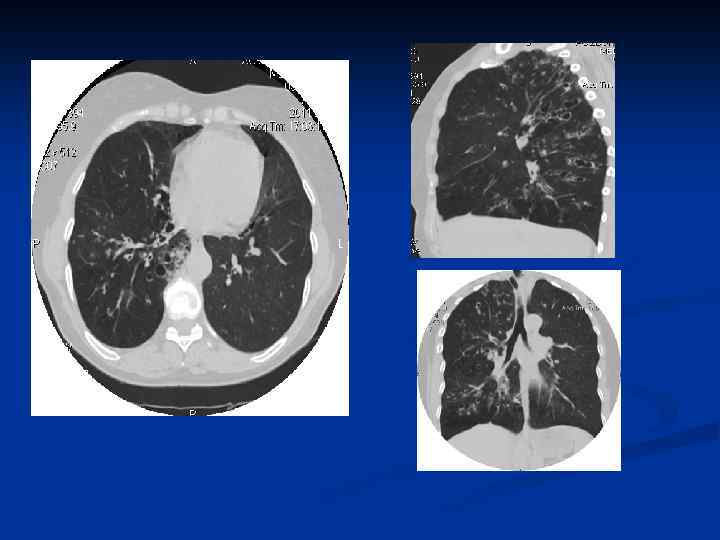

n КТ обладает способностью выявлять все структурные изменения легочной паренхимы, перестройку сосудистобронхиальной архитектоники, уплотнение интралобулярных и перилобулярных перегородок, перибронхиальный и периваскулярный фиброз, буллезные вздутия и эмфизему. На компьютерных томограммах лучше выявляется картина перестройки легочной ткани по типу сотового легкого, чаще всего развивающегося в периферических субплевральных отделах.

n n n Бронх считается расширенным, если его внутренний просвет значительно превышает диаметр сопутствующей ему парной ветви легочной артерии. Бpонхоэктазы выявляются в виде полостей, заполненных воздухом или секpетом. По денситометрической характеристике бронхоэктазы могут быть трех типов: 1) полости, содержащие воздух, выглядят в виде кольцевидных или щелевидных теней мягкотканной плотности, окружающих просветления высокой прозрачности; 2) полости, содержащие мокроту, могут иметь вид кольцевидных или щелевидных образований мягкотканной плотности, содержимое которых приближается к плотности воды; 3) заполняющая бронхоэктазы густая, вязкая мокрота может давать очаговые тени, близкие по плотности к оружающей фиброзной ткани. В этих случаях приходится ориентироваться на общую структуру пораженного участка легкого и архитектонику бронхиального дерева.